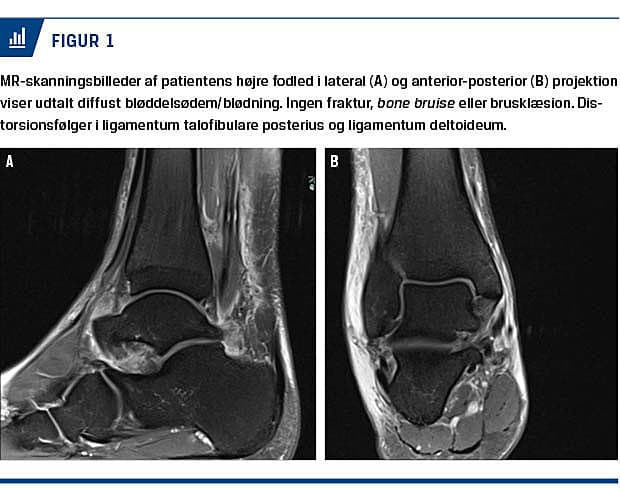

Efter tre dage blev han indkaldt til MR-skanning (Figur 1). Skanningsbillederne blev vurderet af en radiologisk overlæge, som beskrev udtalt, diffust bløddelsødem/blødning omkring fodleddet, især lateralt, diffus signaløgning af ligamentum talofibulare posterius og distorsionsfølger i ligamentum deltoideum. Ingen fraktur, bone bruise, brusklæsion, ledansamling eller senelæsion.